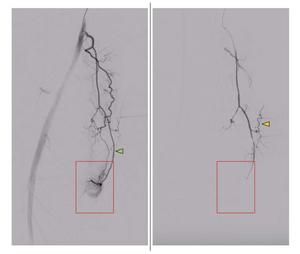

Peri-interventional DSA of the descending genicular artery (DSA), a diagnostic procedure to view the inner surface of blood vessels, (green arrow) in a patient with symptomatic knee osteoarthritis of the right leg. On the left, the pre-interventional image with a clearly visible hyperemic blush (red box). On the right, the post-interventional DSA after embolization with Imepenem-Cilastatin. A completely eliminated blush is observed while preserving skin collaterals (orange arrows).

Credit: Radiological Society of North America (RSNA) and Florian Nima Fleckenstein, M.D.